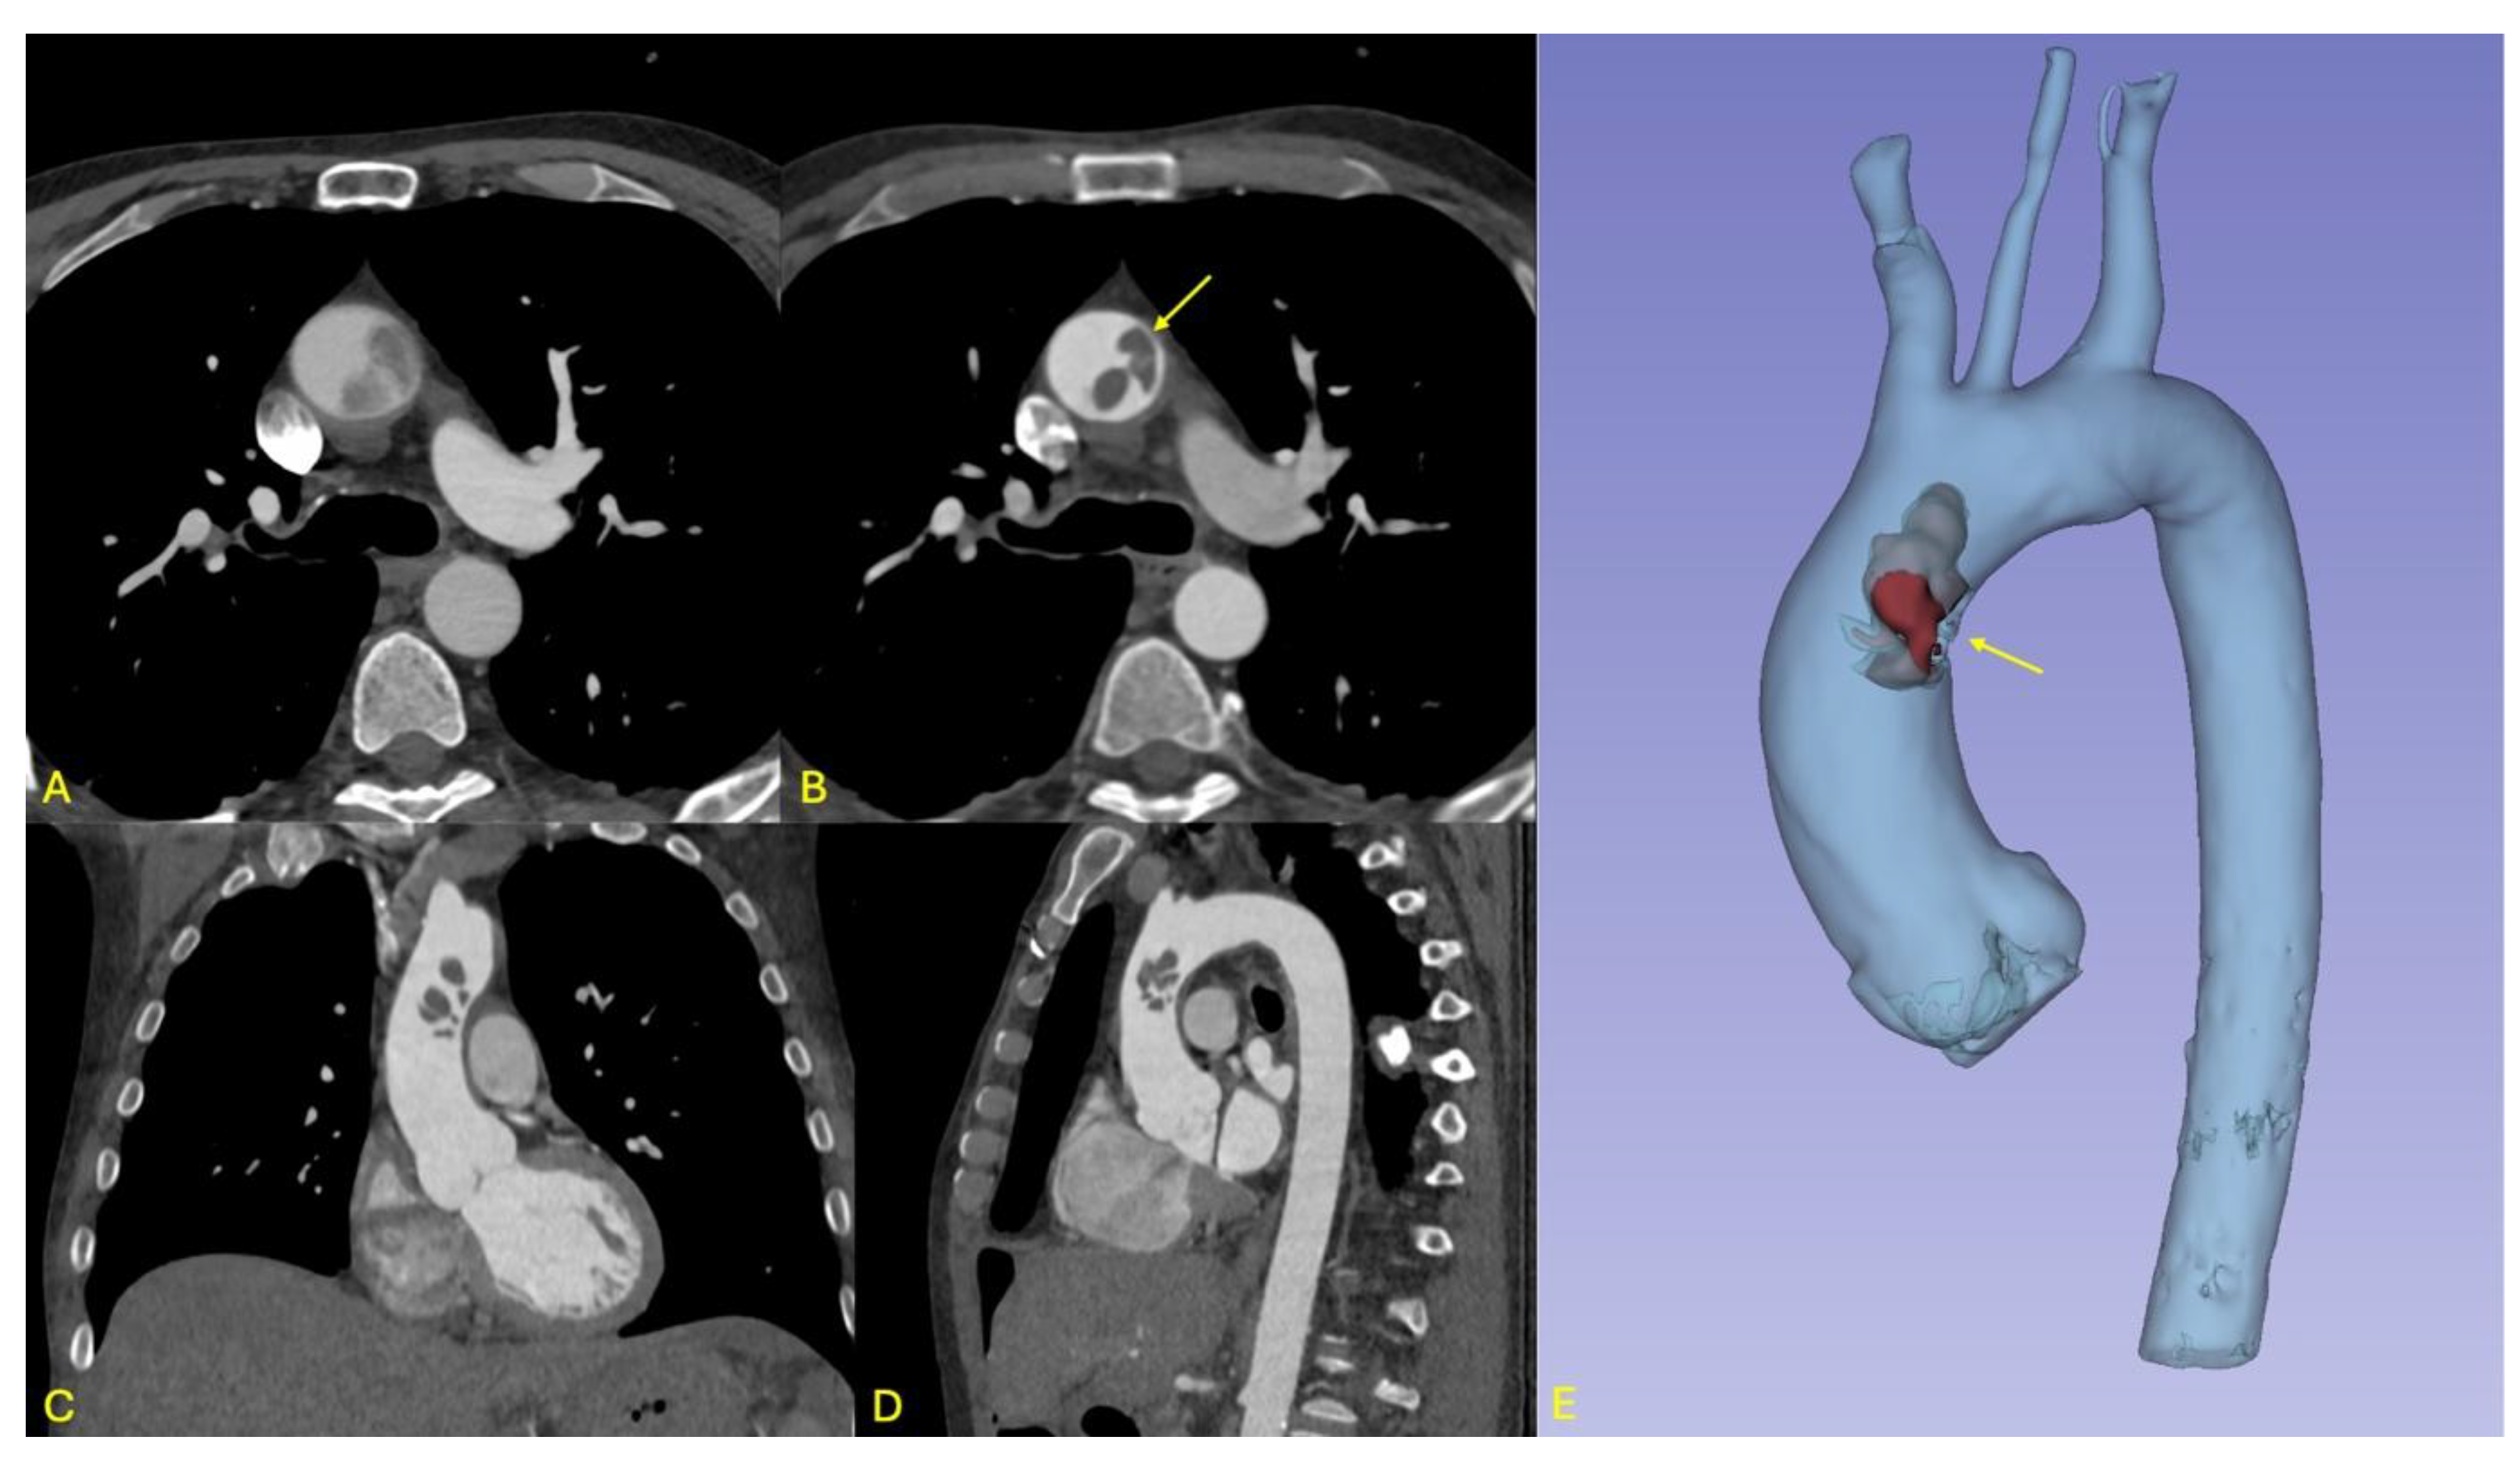

2. PATIENT 1: Surgical Management of Floating Aortic Thrombus